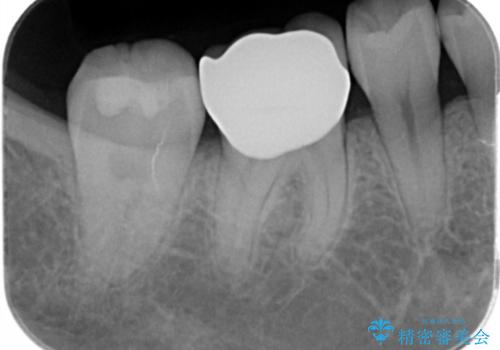

- 過去に退院で治療した詰め物が欠けたことにより来院。

古いプラスチックの樹脂、虫歯を全て取り除き

ジルコニアクラウンにて治療しました。

- ジルコニアクラウン・仮歯 12.1万円費用は治療当時の料金となります